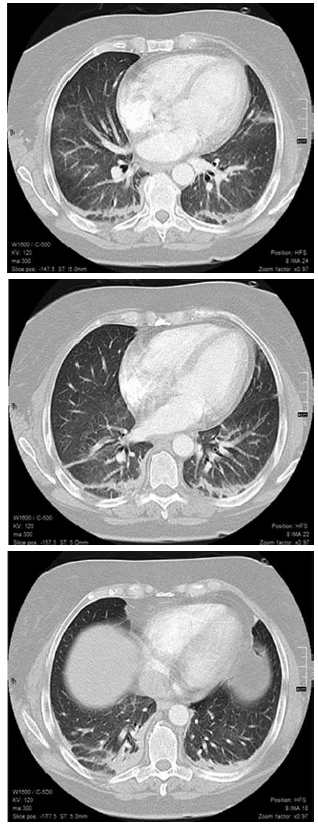

Se realizó una tomografía axial computarizada

(TC) de tórax con protocolo para tromboembolismo

pulmonar (Figura 2).

Dr. Mariano Volpacchio: En las imágenes no

se evidenciaron signos compatibles con tromboembolismo.

No se observa derrame pleural.

Se visualizan imágenes ganglionares en axilas

y mediastino que no alcanzan rango adenomegálico.

El parénquima pulmonar muestra

extensas áreas con densidad vidrio esmerilado.

Se visualizan consolidaciones en segmentos

basales posteriores. A nivel abdomen superior

no se evidencias alteraciones significativas. Las

imágenes inespecíficas podrían corresponder a

neumonitis, o proceso infeccioso, de todas maneras

no puedo descartar otras etiologías como

hemorragia alveolar.

Dr. Mariano Volpacchio: La presencia de infiltrado

bilateral en vidrio esmerilado visto en la

tomografía computarizada de tórax representa

ocupación alveolar, lo que apunta a un diagnóstico

diferencial que incluye edema, hemorragia alveolar

difusa, infección, cáncer (por ejemplo, el carcinoma

broncoalveolar), y enfermedad pulmonar intersticial,

lo cual compromete el espacio alveolar y el

intersticio.